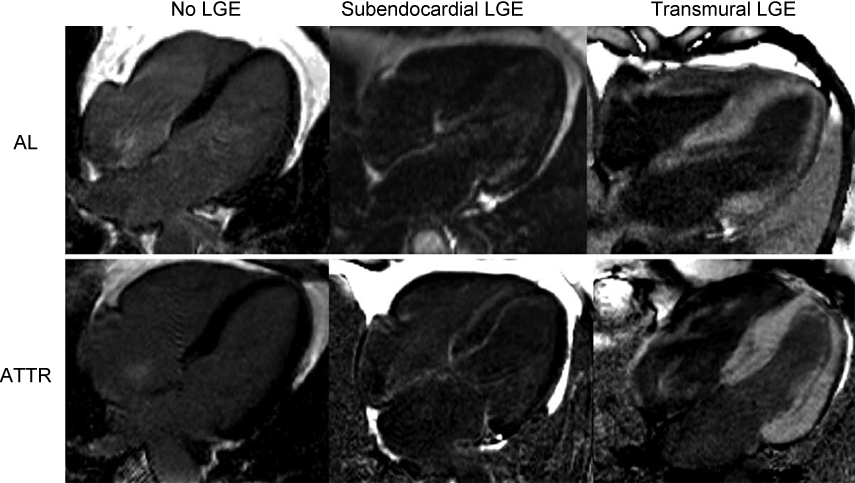

心アミロイドーシスのMRI(ガドリニウム遅延造影)

心アミロイドーシスのMRI(ガドリニウム遅延造影)は予後推定因子となる。

ALアミロイドーシス(上段)とATTRアミロイドーシス(下段)

左:遅延造影なし、中:心内膜への遅延造影、右:貫壁性遅延造影

3患者における特徴的なガドリニウム遅延造影(LGE)

上段:ALアミロイドーシス、下段:ATTRアミロイドーシス

左:LGE(-)、中:心内膜LGE(+)、右:貫壁性LGE(+)

AL、ATTRともにLGE(-)、心内膜LGE(+)、貫壁性LGE(+)パターンを認める。